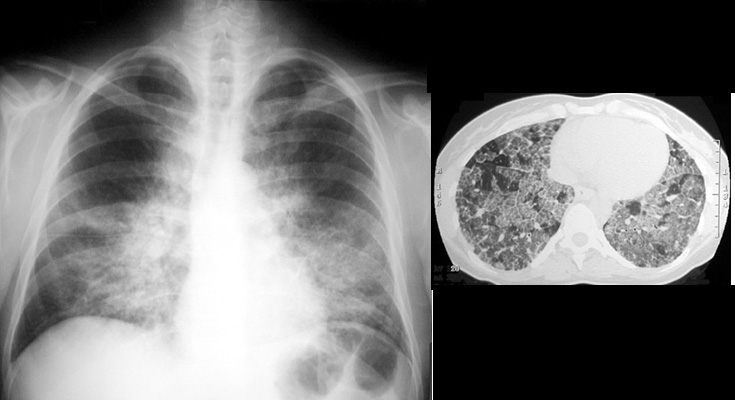

Alveolar ProteinosisBilateral predominantly perihilar and lower lobe lung consolidation is not as symmetric as the usual presentation. CT shows bilateral ground glass lung opacities containing a network of interstitial lines, the "crazy pavement" pattern. |